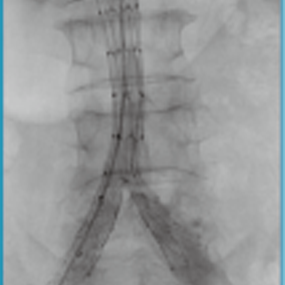

Aegis®/定海石™分叉型大动脉覆膜支架及输送系统

Aegis®/定海石™分叉型大动脉覆膜支架及输送系统适用于瘤体累及髂总动脉的腹主动脉瘤的治疗。

医疗器械名称:分叉型大动脉覆膜支架及输送系统(商品名:Aegis®/定海石™ )

医疗器械注册证号:国械注准20193131931